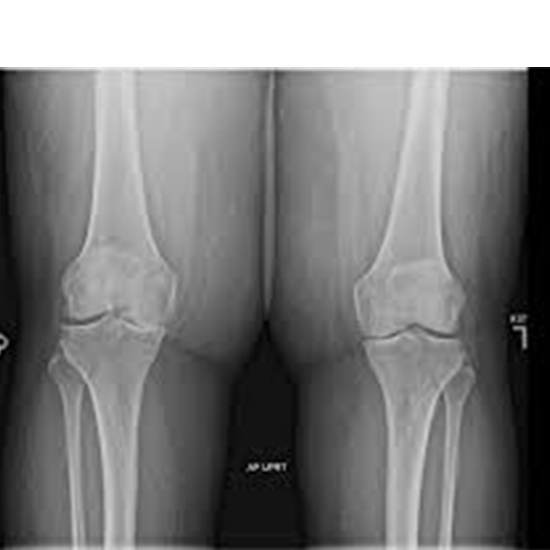

X-ray Both Knee AP View

"An X-ray of the knee joint is a way to see how well it is aligned, how good the bones are, and how much degeneration there is in the knee." When taking an anterior-posterior (AP) view, the X-ray beam is put in front of the patient.

The doctor recommends X-raying both knees AP views to find any broken bones, injuries, osteoarthritis, and other knee problems. Knee problems often cause pain, tenderness, swelling, and a change in the shape of the knee.